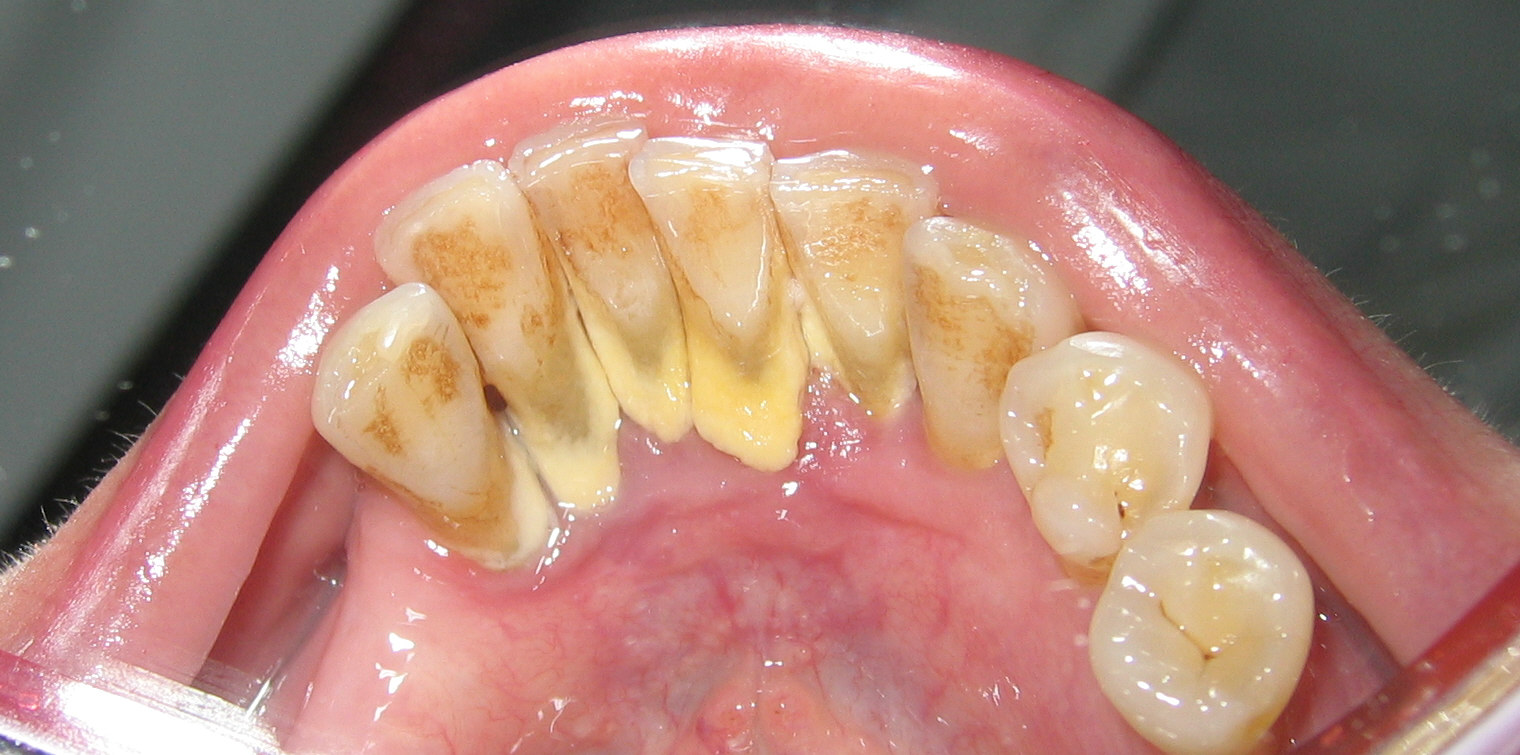

Placa supragingival

Supragingival plaque

(1) Definición:

Es la placa situada por encima del margen gingival.

(1) Definition:

Supragingival plaque is bacteria adherent above the gingiva, whereas bacteria below the gingiva is called subgingival plaque.